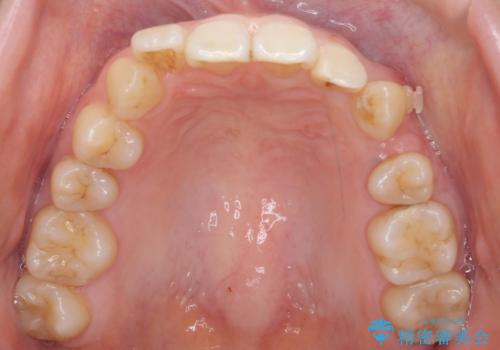

- 前歯のがたつきを主訴に来院。

下の前歯は生まれつき1本少ない状態でした。

左上の犬歯が入りきらずねじれており、かみ合わせもずれていました。

左上の小臼歯を1本抜いて治療しています。

前歯は内側に傾いており(ラビッティング)、過蓋咬合(深いかみ合わせ)を呈していました。

難しい治療でしたが綺麗に咬み合わせることができ、また前歯もしっかり当たるように治療できました。